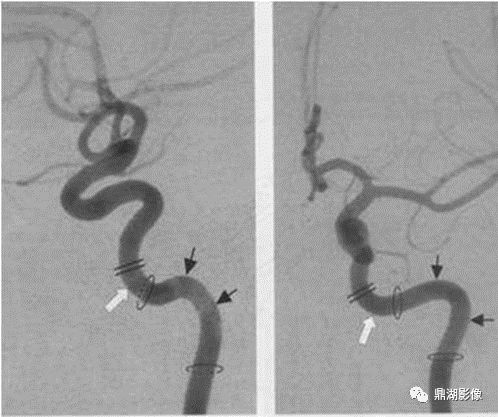

完整汇总 | 颈部及颅内动脉影像分段